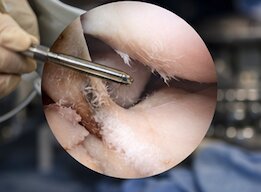

Arthroscopic (Keyhole) Surgery

Minimally invasive arthroscopic procedures enable treatment of ligament injuries, meniscus tears, shoulder instability, and rotator cuff problems through small incisions with faster recovery.

Arthroscopic Knee Surgery

Meniscus Repair & Cartilage Procedures

Shoulder Arthroscopy